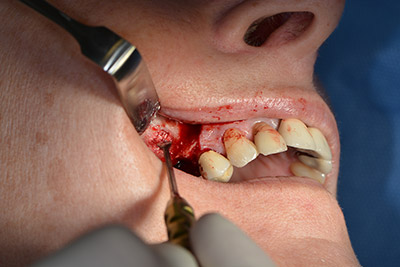

The following holes were drilled at a reduced speed of 300 rpm. The Implantmed demonstrated its true capability at this stage. The surgical protocol can be preset – the various positions can be selected simply by pressing the “P” position of the foot control (Fig. 10 to 11).

The next programmed position is the placement of the implant and in our practice it is preset to a force of 32 Ncm (Fig. 12).